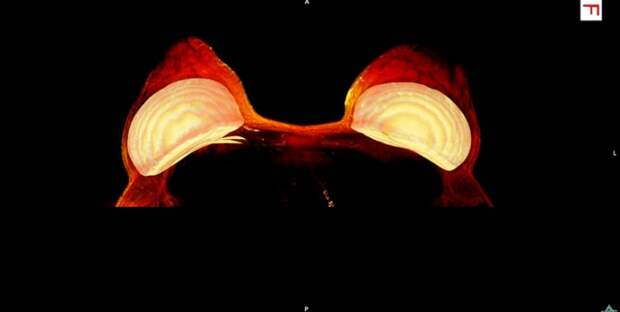

4. Грудные импланты, заснятые при помощи аппарата МРТ